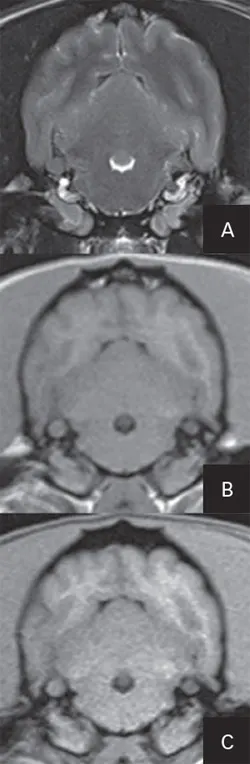

Transverse MRI at the level of the tympanic bullae: T2-weighted image (A), a T1-weighted image (B), and T1-weighted, fat-suppressed, postcontrast image (C). Note that the tympanic bullae are bilaterally affected with T2-hyperintense, T1-isointense to gray matter material that is noncontrast enhancing. These imaging characteristics are consistent with PSOM.